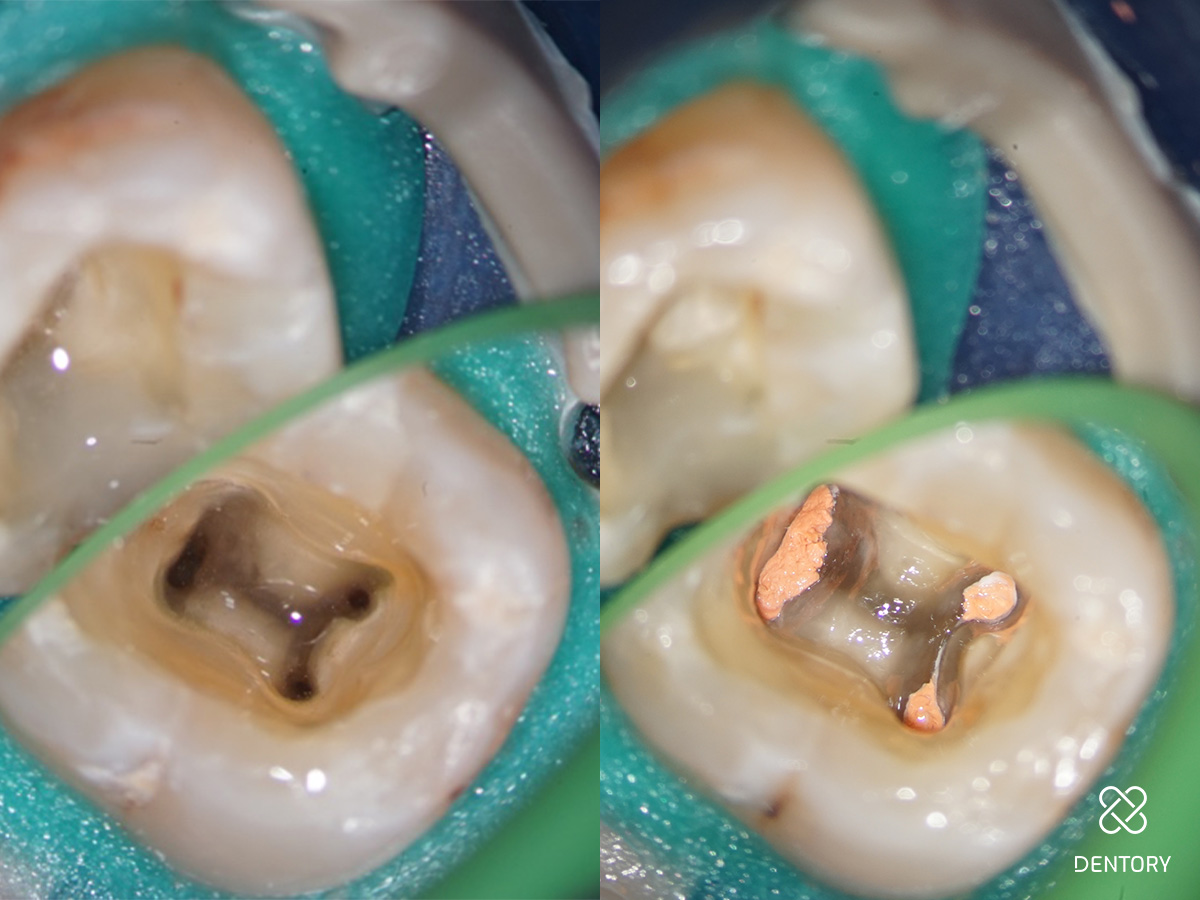

Abbildung 1

Diagnoseaufnahme (alio loco) Regio 37: Symptomatische apikale Parodontitis (PAI 4). Als Besonderheit erkennt man bereits die S-förmige Kanalkrümmung in der mesialen Wurzel und die J-förmige apikale Krümmung im distalen Kanal.

Abbildung 3

Aufbereitung des distalen Kanals: Es ist darauf zu achten, die Kontaktzeit im Kanal kurz zu halten sowie den Kanal abschnittsweise von koronal nach apikal zu bearbeiten. Zusätzlich verhindert eine regelmäßige Rekapitulation mit einer Handfeile bis zur endometrisch bestimmten Länge eine Verblockung des Kanals mit Debris.